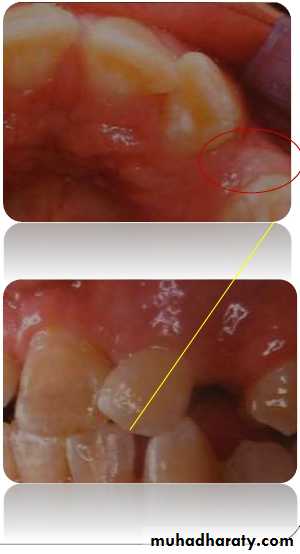

Inspection

Non-appearance of

permanent canine clinicallyby its eruption age.

Presence of antimere.

Presence of anterior spacing

for a long period.Persistent median diastema.

Abnormal morphology of

lateral incisor or presence of

peg laterals.

Improper angulations of

45Palpation

Bulge of permanent Canine could be palpatedbuccally above the deciduous canine 2-3 yrs

before its eruption.

It should be palpated deep above attached

gingiva in the sulcus where mucosa reflects. Deciduous canine should be checked for

mobility. Palpation should be done in abnormal

locations after getting clue from inspection.